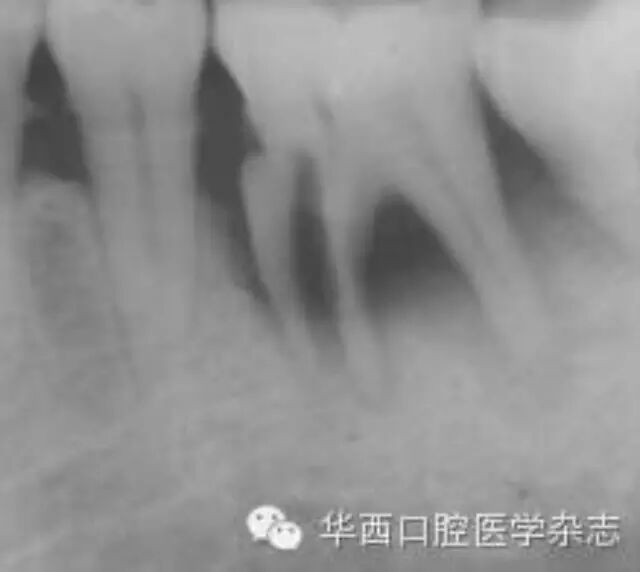

牙根折裂好发于下颌第一磨牙的近中根及上颌第一磨牙的近颊根、腭根,也可见于第二磨牙、前磨牙等(图12)。可以单发,也可对称性多发(图3)。可以是双侧的同名牙,也可以是同侧的上、下颌同名牙或相邻牙(图45)。

左:36牙近中根管下段内径增宽;右:36牙折线明显,折片向近中移位,伴牙槽骨吸收。

1 36牙近中根牙根折裂

牙根折裂早期仅见根尖孔扩大、根管内径的部分扩大,折线常沿牙根长轴向冠方纵行。随着病变发展,折片分离,多向远端移位,常伴根周及根分叉牙槽骨吸收;也可见斜折或横折,横折者多伴发牙槽骨重度吸收,可见于前磨牙或前牙。根管治疗后的牙根折裂线可表现为充填牙胶的侧方出现缝隙,继而出现根管内径增宽。底穿、侧穿以及桩钉路径偏移引起的折裂常沿病变走行;长烤瓷桥的受力不均也可发生牙根折裂[3](图6)。